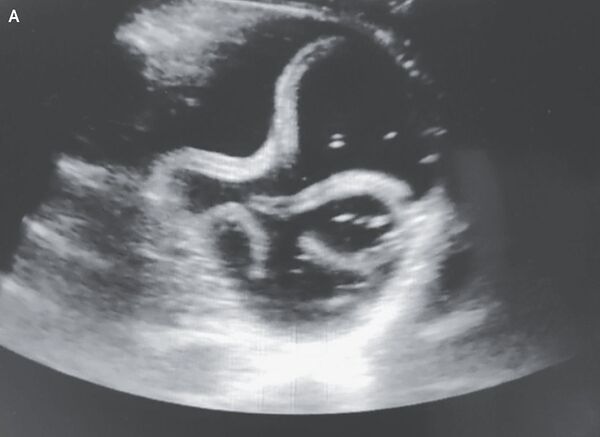

Os médicos fizeram ultrassom da sua veia cava inferior, uma grande veia perto do abdômen, para verificar os níveis de líquido em seus vasos sanguíneos. Mas, durante este processo, eles observaram uma "estrutura [...] tubular que se movia com um movimento enrolado" dentro do estômago, escreveram os autores.